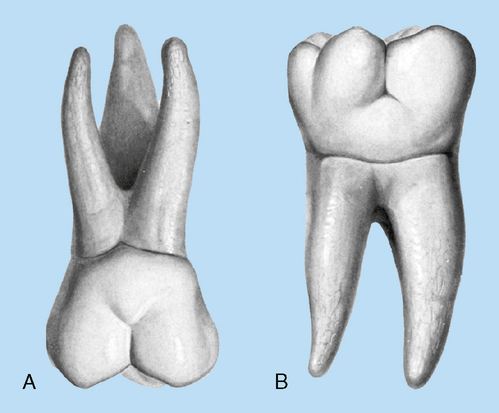

Product Item: First cheap molar teeth

Need some advice for a badly decayed first molar tooth cheap, 6 Year First Molars First Permanent Teeth Wainright Wassel DDS cheap, Baby teeth chart What order do teeth come in BabyCenter cheap, The Different Types of Teeth and What They Do Advantage Dental cheap, 6 Year Molars The First Adult Permanent Teeth Dentist in Great cheap, Mandibular First Molar an overview ScienceDirect Topics cheap, Where Are The First Molars In The Mouth ArchWired cheap, Maxillary first molar Wikipedia cheap, 12 The Permanent Mandibular Molars Pocket Dentistry cheap, First molar never the first Tooth Easy Dental Specialist cheap, First Molar an overview ScienceDirect Topics cheap, First Molar Single Implant First Molar Single Implant Kazemi cheap, First Molar Images Browse 93 882 Stock Photos Vectors and cheap, What is a molar teeth Dr Jamilian cheap, Tooth Anatomy Gosford Experienced Dentists VC Dental cheap, Deciduous Mandibular First Molar Dental Education Hub cheap, Family s Campus Oral Health Care Zone for Grown ups cheap, Dentistry Journal Free Full Text Uprighting an Impacted cheap, All about primary teeth Gorbatov Dentistry Your Dentist in cheap, Sectioning and Extraction of Maxilary First Molar with Steven T. Cutbirth DDS cheap, First Molar Images Browse 98 270 Stock Photos Vectors and cheap, 15 Molars Pocket Dentistry cheap, Anatomy and Development of the Mouth and Teeth Stanford Medicine cheap, Salvaging a Periodontally Compromised and Endodontically Involved cheap, All About Primary Teeth Triangle Pediatric Dentistry cheap, Kids Corner Indianola Family Dentistry cheap, Hand Instrumentation of First Molar Teeth Dimensions of Dental cheap, Morpho 106 Copy Austin Dental Careers cheap, Back Implant Crown Left Molar Male cheap, Stages of Teething and Helpful Hints Kids Dental Online Plano cheap, Baby teeth chart What order do teeth come in BabyCenter cheap, Tooth Eruption and Shedding Barkoff Dental in Syosset NY cheap, Asymmetrical Extraction in an Adult Class II cheap, Dental Anatomy Mandibular First Molar INBDE cheap, Case Study 84 Missing a lower right first molar and camouflaged cheap.

First cheap molar teeth